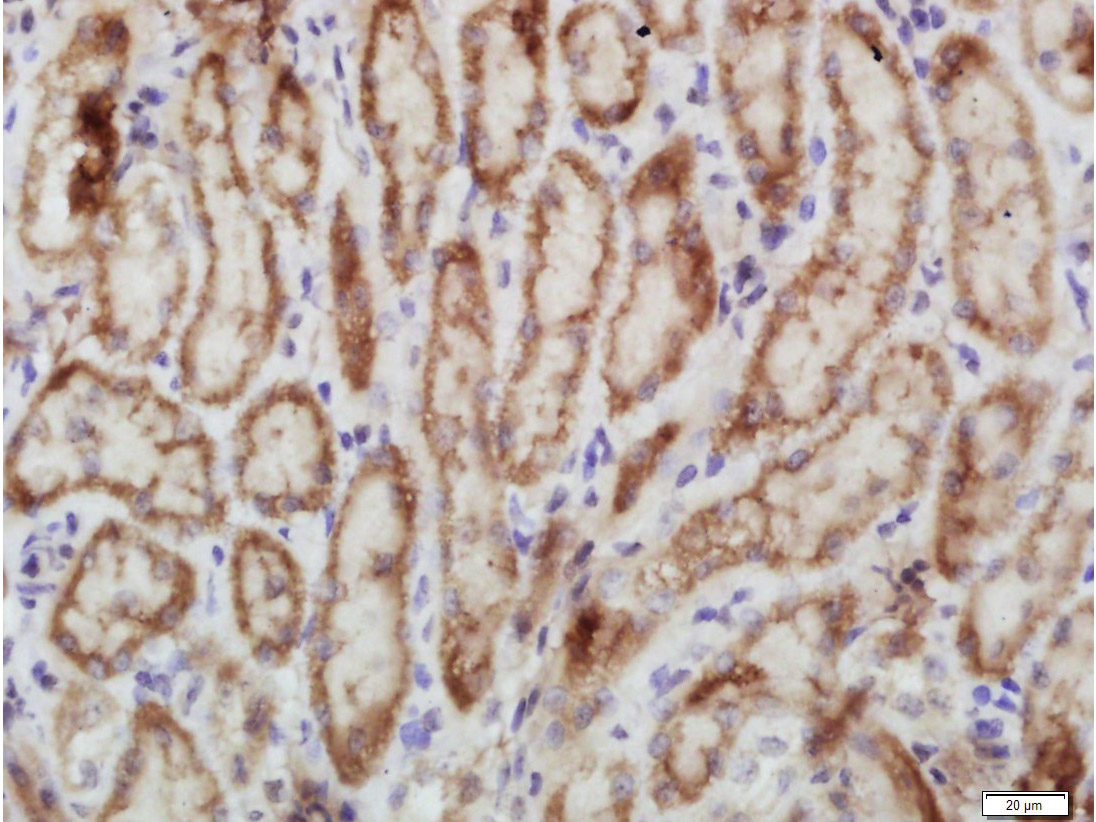

| IHC-P | Human, Mouse, Rat | Rabbit, Pig, Cow, Dog | 1:100-500 |

| IHC-F | Human, Mouse, Rat | Rabbit, Pig, Cow, Dog | 1:100-500 |